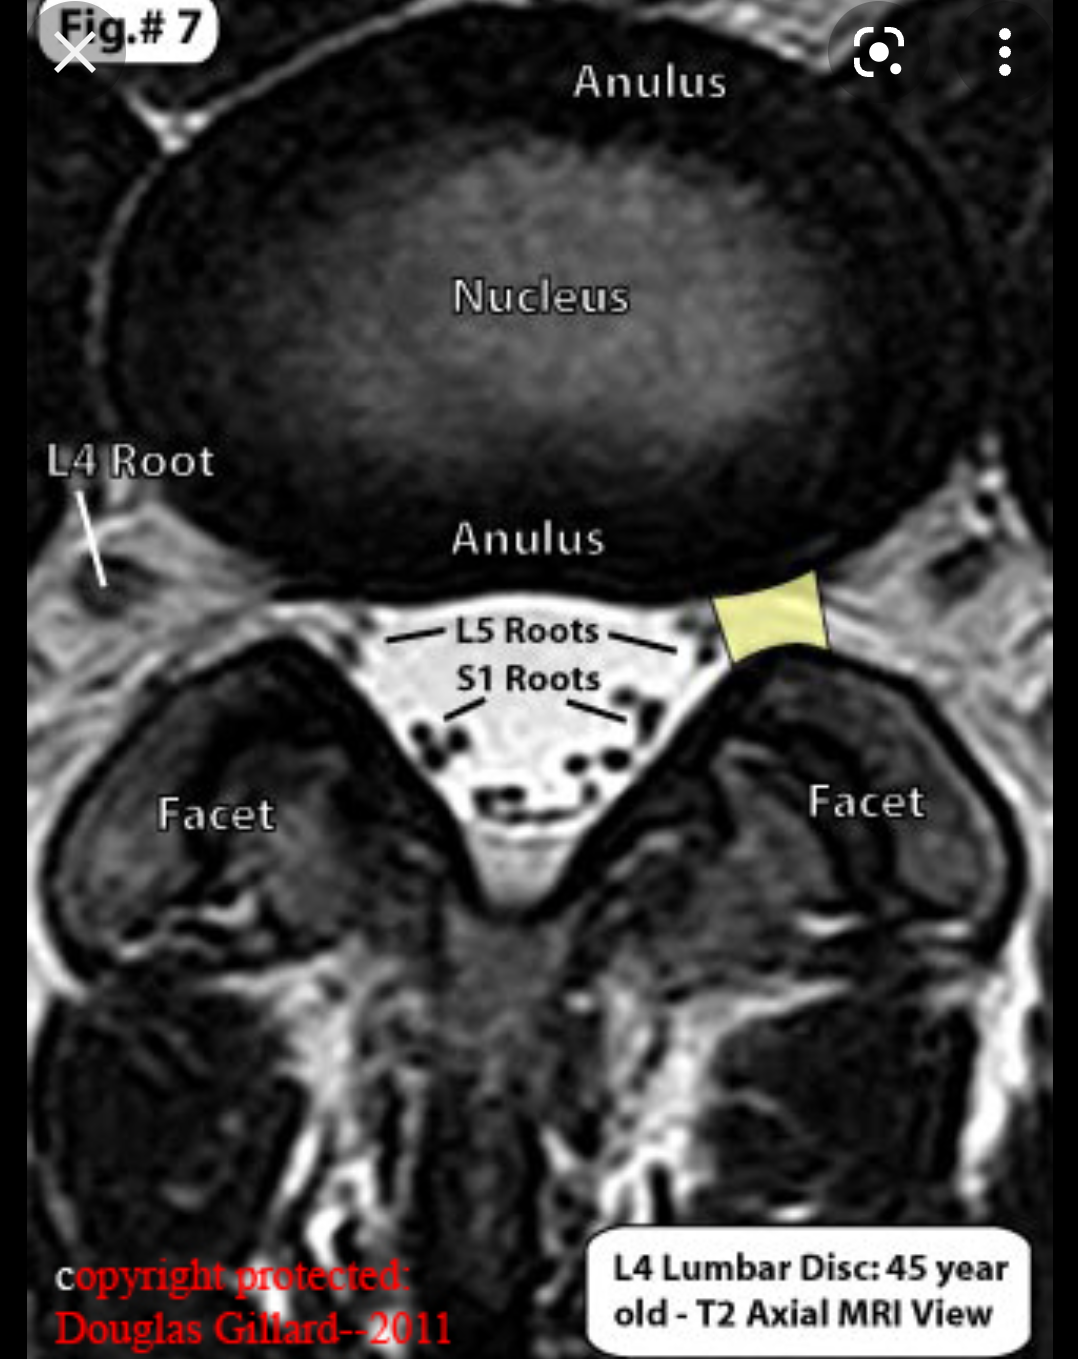

Тук можеш да видиш разликата между фораминална и екстрафораминална:

Също ѝ викат латерална на екстрафораминалната.